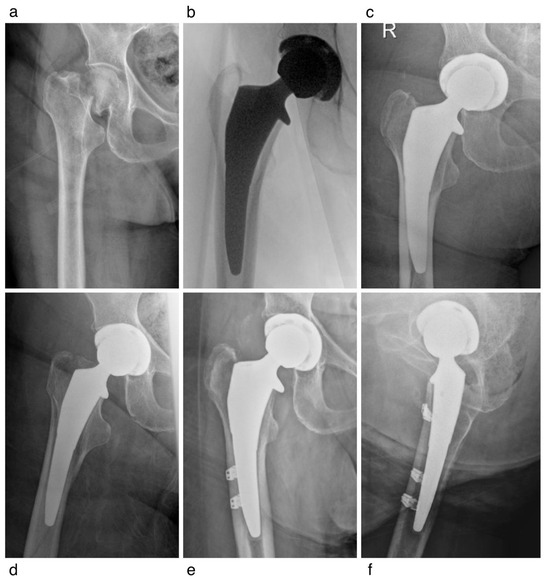

A Modern Collared Cementless Femoral Stem for the Arthroplasty Treatment of Femoral Neck Fractures

Background/Objectives: For femoral neck fractures (FNFs) treated with hip arthroplasty, cemented femoral fixation is frequently recommended due to its association with reduced early perioperative fracture and reoperation rates. However, newer-generation collared, cementless triple-tapered (CCTT) stems may present benefits compared with conventional press-fit designs. This study sought to assess 30-day survivorship of a CCTT stem in patients undergoing hip arthroplasty for FNF via the direct anterior approach (DAA). Methods: We conducted a retrospective review of all patients who underwent hemiarthroplasty (HA) or total hip arthroplasty (THA) for displaced FNF from 2019 to 2023. All procedures were performed through the DAA using a hydroxyapatite-coated CCTT femoral stem. The primary outcome was 30-day stem survival. Secondary outcomes included reoperation, stem revision, complications, readmission, and radiographic outcomes including intraoperative and postoperative periprosthetic fracture and subsidence. Results: A total of 184 patients were included (mean age 76.1 ± 10.0; 70.1% women). THA was performed in 77.7% and HA in 22.3%. At 30 days, no stems required revision. The 30-day reoperation rate was 3.5% (5/184). There were four intraoperative fractures: 3 (1.6%) Vancouver AG and 1 (0.5%) calcar. Postoperatively within 3 months, seven fractures occurred: five (2.7%) Vancouver AG and two (1.1%) Vancouver B1. Conclusions: Use of a modern CCTT femoral stem for FNF demonstrated excellent early survivorship with low rates of intraoperative and postoperative periprosthetic fracture, comparable to published outcomes of cemented fixation. These findings suggest that this stem design may represent a safe and efficient alternative to cemented femoral fixation in FNF. Further studies are warranted to evaluate mid- and long-term outcomes. Full article

Show Figures

Figure 1